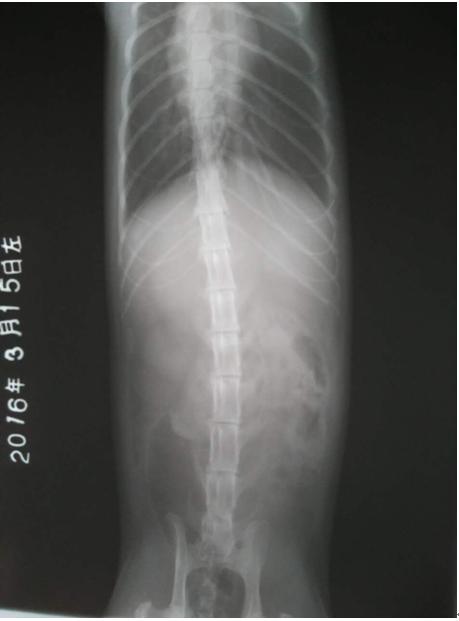

3、在条件允许的情况下,应定期对患猫做X射线、B超复查, 以便了解该病的预后状况,若出现异常情况要及时做出适当的处理。